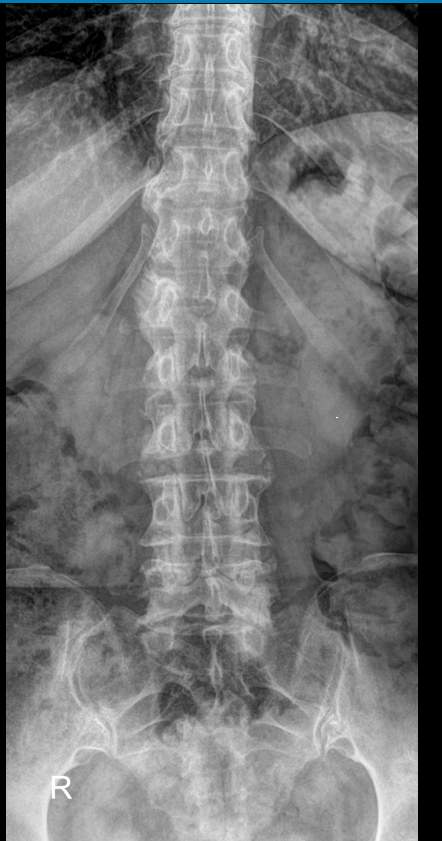

Поясничные позвонки, с 1 по 5, самые крупные во всем позвоночнике, так как удерживают большой груз ― всю верхнюю половину тела. Это последние отдельные позвонки, следующие 5 крестцовых позвонков срастаются в единую крестцовую кость. Благодаря массивности поясничный отдел может выдержать довольно сильные удары, однако травмы наблюдаются и в этом месте. Но большая часть патологий поясницы вызвана хроническими дегенеративно-дистрофическими изменениями. И чаще всего они развиваются в пояснично-крестцовом сочленении.Увидеть произошедшие с позвоночником изменения позволяет рентгенография. На снимке обычно видны все 5 поясничных, 12-й грудной и 1-й крестцовый позвонки. В некоторых случаях врачу необходим обзор крестца до уровня 3-4 позвонков. Снимки выполняются всегда в 2 проекциях.

Что покажет рентген поясничного-крестцового отдела позвоночника

• Сохранение или изменение поясничного лордоза;

• Признаки сколиоза: искривление оси позвоночника, в какую сторону, на сколько градусов, на уровне какого позвонка, с ротацией или без;

• Признаки нестабильности в поясничном отделе позвоночника

• Изменение высоты тел позвонков и межпозвонковых дисков ;

• Дистрофические изменения тел позвонков, костные разрастания, склероз;

• Наличие грыж Шморля;

• Травматические повреждения;

• Новообразования.